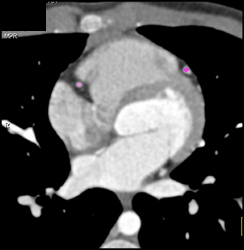

Diagnosis

Enlarged Lv